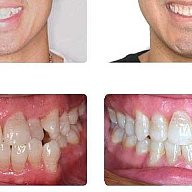

Брекеты

11 photos